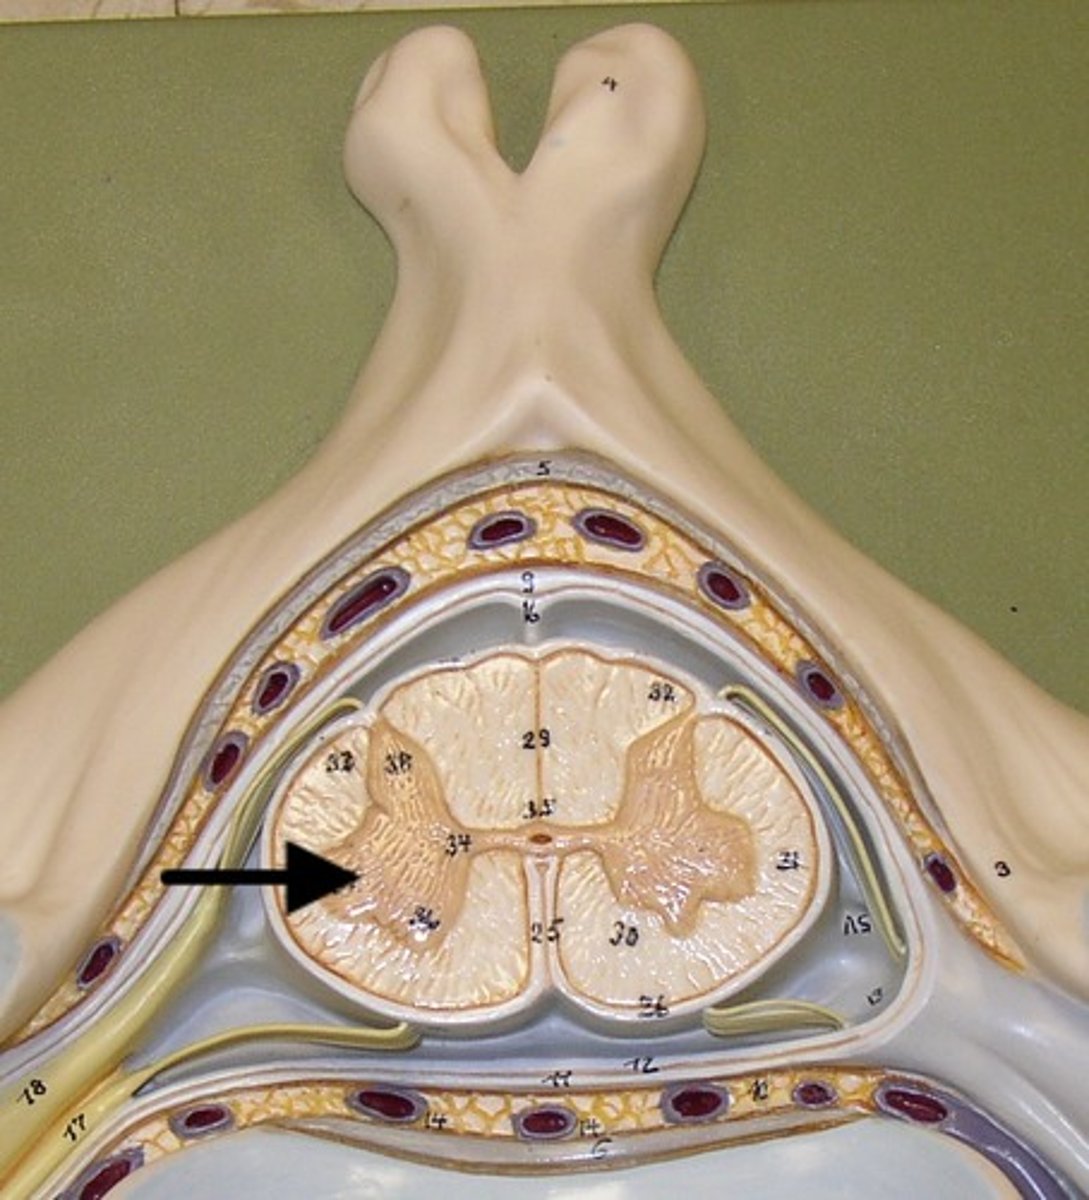

posterior gray horn

anterior gray horn

lateral gray horn

gray commissure

Part of grey matter connecting the two halves of the grey matter in spinal cord

posterior root

axons of sensory neurons

posterior root ganglion

anterior root

axons of motor neurons

spinal nerve